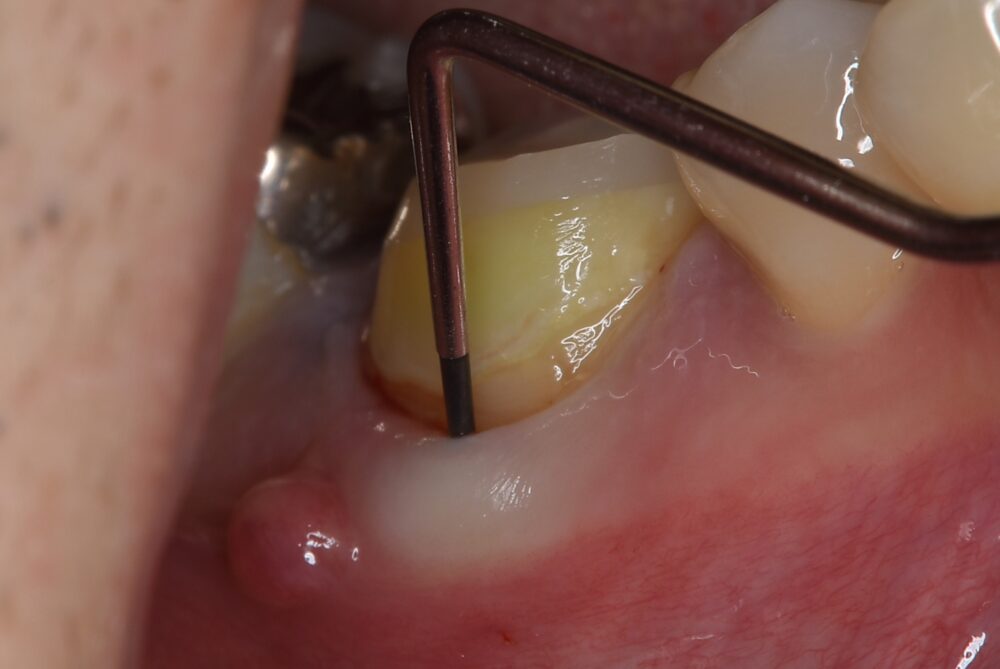

症例1:パーフォレーションリペア症例

(歯の中に大きな穴が空いてしまっているのを埋めて再生を促す治療)

歯に穴が空いていて骨に炎症がある状態 |

CTでも歯の周囲に骨がないのが分かる。 |

人為的根穿孔を起こした部分に感染を起こしており、歯周ポケットが9㎜ありました。 ラバーダム防湿とマイクロスコープを使用して丁寧に治療を行いました。 殺菌性があり歯を補強することのできるMTAという根管充填材料を使用して、歯周ポケットは2㎜に改善しました。 |